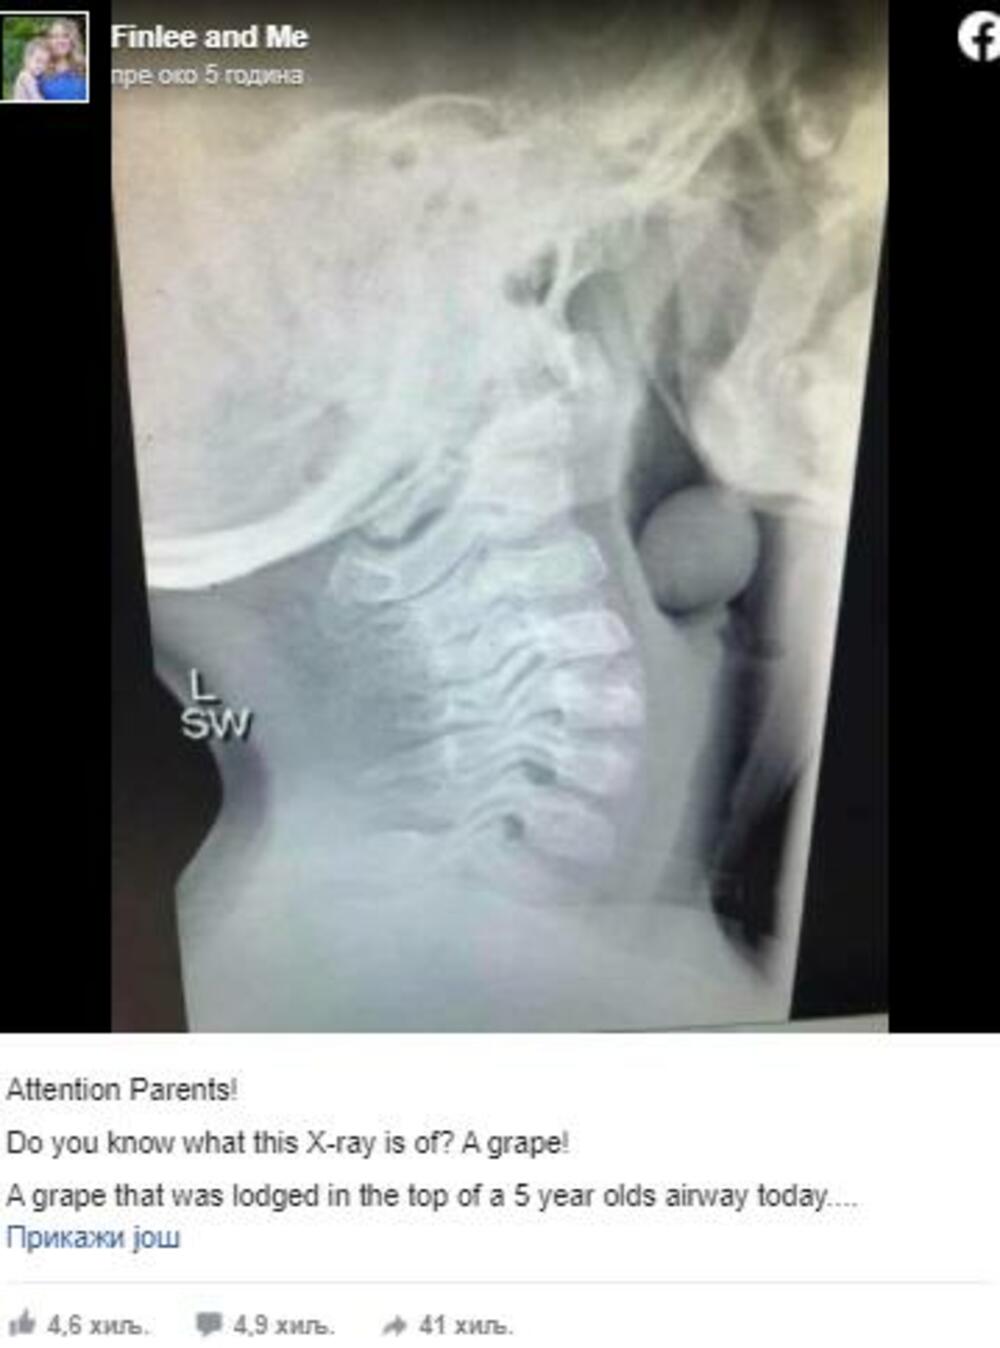

Njegova majka, Angela Henderson, je na Facebook stranici Finlee and Me podelila rendgenski snimak svoga deteta kako bi upozorila roditelje da budu oprezni kad daju svojoj deci određene namirnice

Poželjno je biti na oprezu kad je u pitanju bilo koja hrana koja se nađe ispred vašeg deteta. Međutim,grožđe je voće koje je poznato po tome da se dete sa njim može ugušiti. Zbog svog oblika i veličine ono se s lakoćom može zaglaviti u dečjm dišnim putevima. U slučaju ovog petogodišnjaka bobica grožđa je zapela u njegovom dušniku, između grkljana i prsne kosti. Njegova majka, Angela Henderson, je na Facebook stranici Finlee and Me podelila rendgenski snimak svoga deteta kako bi upozorila roditelje da budu oprezni kad daju svojoj deci određene namirnice.

U svojoj objavi je napisala: „Znate li šta je na rendgenskom snimku? Grožđe!"

Ovaj put je dečak imao sreće što je deo njegovog dušnika ipak ostao prohodan pa je mogao disati. Bez obzira na to, morali su ga staviti pod anesteziju kako bi mogli ukloniti bobicu.